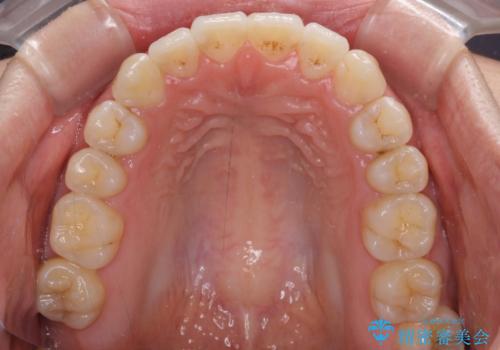

前歯のデコボコを治したい ワイヤー矯正

奥の銀歯も気になっていたため、矯正治療後にセラミッククラウンにて補綴することとしました。

1年半程度の期間を見込んでいましたが、上下の真ん中の位置をできる限り合わせるための調整に少し時間がかかってしまいました。

咬み合わせが安定し、前歯の汚れも付きにくくなりました。